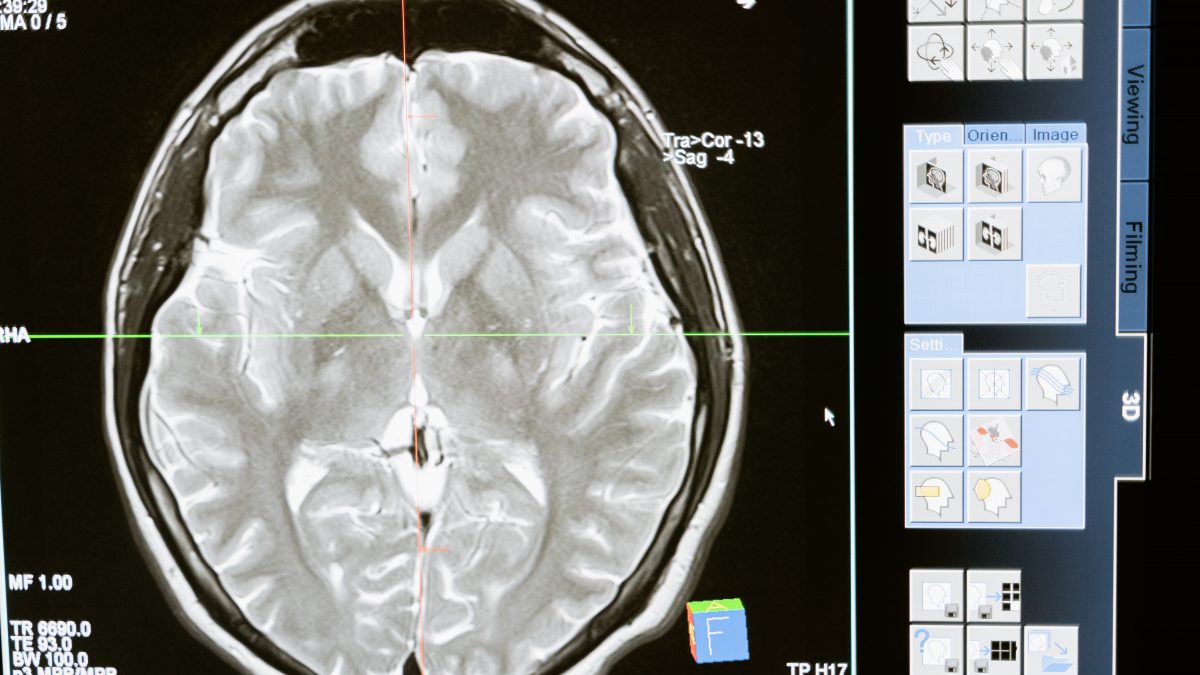

26 enero, 2023Que el cerebro es un órgano fascinante no es un misterio. Para el médico y filósofo griego Hipócrates, era el “trono” de la inteligencia, la experiencia y la conciencia, y quizás estaba en lo cierto. Es la cuna del pensamiento, de la razón y del lenguaje. Es el titiritero que mueve los hilos para que ejecutemos acciones que nos resultan tan sencillas como comernos la entrañable paella de nuestra abuela o correr para coger el autobús. Nos ayuda a discriminar ciertas cualidades sonoras de nuestro entorno y, en definitiva, nos permite disfrutar de la vida.

Desafortunadamente, nada es para siempre y algunas de las áreas cerebrales, como el lóbulo parietal, sufren un deterioro en la enfermedad de Alzheimer. Este lóbulo es el encargado de procesar principalmente información somatosensorial, es decir, maneja datos sobre el tacto, el movimiento y la posición de nuestro cuerpo en relación al espacio. Además, también procesa información cognitiva y multimodal (que procede de distintas modalidades sensoriales).

El lóbulo parietal es tan importante que algunos investigadores señalan que la reducción de flujo sanguíneo en esta zona podría servir como biomarcador para detectar el alzhéimer en sus etapas más tempranas.

En las personas con una discapacidad visual, el lóbulo parietal no se deteriora, sino que sufre un remodelado fruto de los mecanismos neuroplásticos cerebrales. Estos mecanismos no son otra cosa que la capacidad que tiene el tejido nervioso para reforzar sus conexiones y crear otras nuevas. Es bien sabido que esta plasticidad neuronal puede surgir tras una lesión y como consecuencia de la experiencia.

Todo lo anterior reforzaría sus conexiones neuronales a favor del lóbulo parietal. Así, se ha observado que en las personas con una pérdida visual las conexiones parietales con el lóbulo occipital se refuerzan, lo cual es una prueba de la denominada neuroplasticidad.